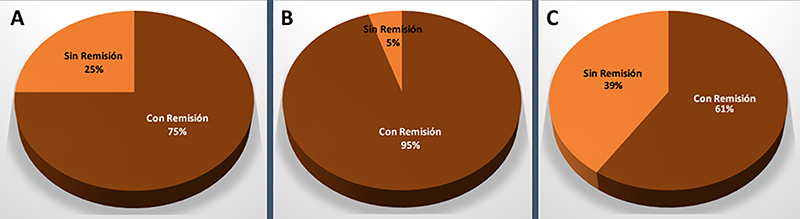

En los pacientes acromegálicos (n=52), de los cuales 21 fueron microadenomas y 31 macroadenomas, se logró con cirugía una tasa de remisión global del 75% (n=39); siendo la remisión para microadenomas del 95% (n=20) y para macroadenomas del 61% (n=19) (graf. 3). En los pacientes que no se logró remisión con cirugía, se registró un Knosp alto en el preoperatorio en todos los casos (n=13). Estos últimos se encuentran bajo terapia multimodal.

Gráfico 3: Resultados en pacientes acromegálicos. A: Remisión bioquímica global. B: Remisión bioquímica en el caso de los microadenomas. C: Remisión bioquímica para los macroadenomas.

En la literatura mundial las tasas de remisión bioquímica global en acromegalia van del 42 al 83%.4,11,28,30,32,33,37,39,42,50,52,53,56,58 Nosotros obtuvimos una tasa de remisión global del 75%, valor que se encuentra dentro del rango obtenido por centros internacionales especializados.

Nomikos et al. encontró una correlación significativa entre tamaño del adenoma y tasa de remisión: 75,3% en microadenomas, 48,6% en macroadenomas y 8,3% en gigantes.49 Jane et al, en un estudio multicéntrico, describe una tasa de remisión del 100% para microadenomas, 61% para macroadenoma y 45,5% para los mayores a 2 cm.37 En nuestra serie se logró la remisión en 95% de los microadenomas y 61% de los macroadenomas, lo que se asemeja a esto último.

Finalmente, cabe destacar que diversos estudios mutivariados6,47,59 concluyen en que la invasión del seno cavernoso es un predictor de no-remisión. En este sentido, el equipo de Erlagen demostró que las tasas de remisión que obtuvieron del 72,2% en adenomas no-invasivos, cayeron a un 21,6% en los invasores.49 En nuestra serie, en la totalidad de pacientes acromegálicos sin remisión (25%, n=13) se evidenció un Knosp alto.